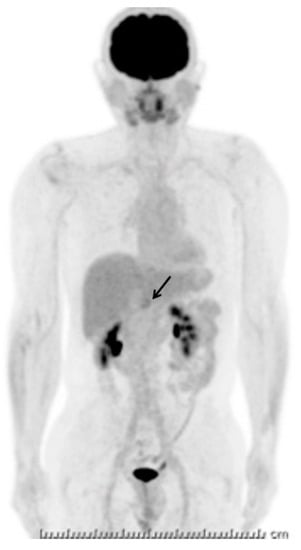

| FDG-PET | 18F-fluorodeoxyglucose-positron emission tomography |

2. Case Presentation